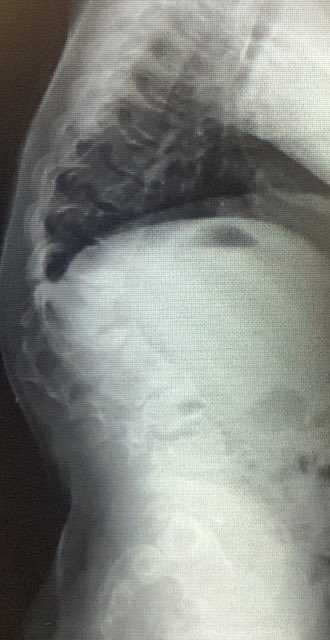

47 years old male patient, neglected (3 mounths) multilevel thoracolumbar junction spine fracture (L1, T12 and endplate of T11). there is monosegmental pure osseous failure of the posterior tension band in T12. this also called "Chance" fractures. #spinesurgery #spine